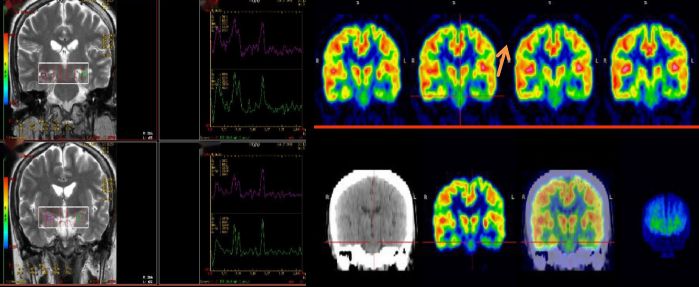

神經系統疾病:

癲癇灶定位,阿茲海默病與帕金森病早期診斷、預后判斷與療效評價,其他腦代謝功能障礙性疾病的評估等。

25歲,男,癲癇反復發作 MRS:雙側海馬區NAA降低,提示:神經元缺失;PET顯像提示:左側顳葉代謝減低,手術切除,術后病理提示符合局部腦組織缺氧病理改變,術后患者明顯好轉。